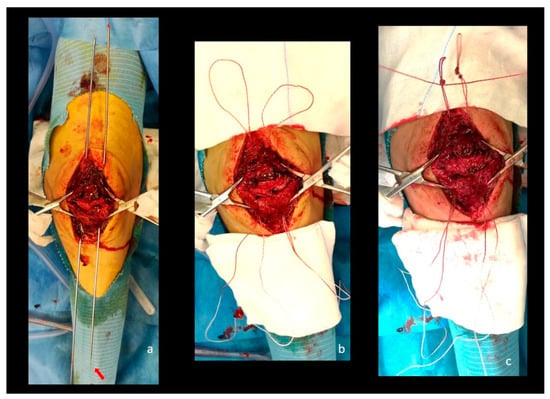

Figure 4.

Clinical picture showing the phases described in the previous figure. (a) Two shuttle wires passing through the patella connected at the distal end with shuttle sutures attached to the looped FiberWire (red arrow); (b) No. 5 FiberWire sutures are passed through the patella with a loop on the upper pole; (c) a noose is created on the upper pole to prevent the lower migration of the FiberWire sutures. Note the third FiberWire passing through the inferior part of the nooses.